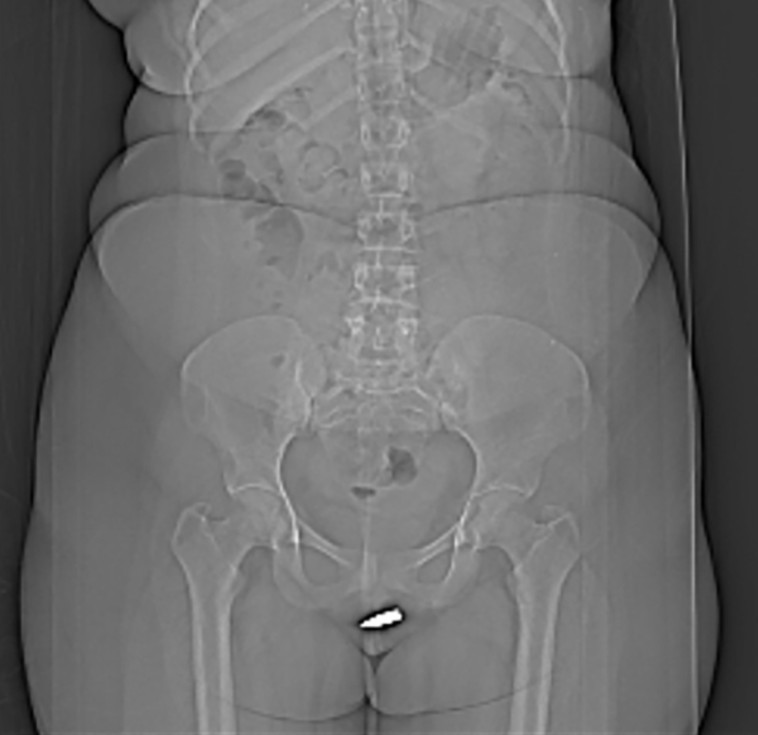

אישה מסומליה נאלצה לעבור ניתוח חירום לאחר שנורתה בטעות באיבר המין בעודה נחה בביתה. הדו"ח, שבו פרטי הפציעה, נחשף לאחרונה ב-International Journal of Surgery Case Reports. "למיטב ידיעתנו, זוהי פציעה כתוצאה מירי והקליע פגע באיבריה המוצנעים של הקורבן", נכתב במסמך.

המטופלת, אלמונית בת 24, נחה בסלון ביתה כשלפתע כדור תועה חדר את תקרת הבית ופגע בה באיבר מינה. הצעירה המודאגת התקשרה למוקד החירום וחובשים שהגיעו למקום פינו אותה לבית החולים ארדואן במוגדישו, שם נערכה לה בדיקת CT שחשפה את הקליע שפגע ישירות באיבר מינה.

תוצאות בדיקת ה-CT הציגו את הקליע